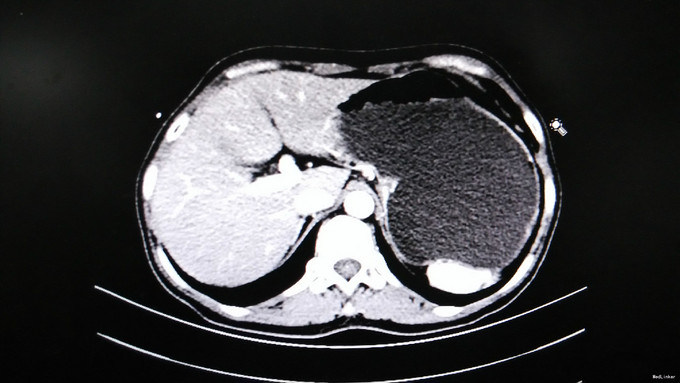

查体及专科情况无特殊 胃肠动力研究中心结肠传输时间检测:48小时和72小时钡条排除率为0%,考虑慢传输。 直肠肛管测压/感觉检测报告:1.肛门指检可见外痔,未及内痔,肛缩有力,力排松弛欠佳;2.测压:肛管静息压正常,直肠静息压偏高,缩肛时肛管压力升高,持续力可,模拟排便时直肠压力升高,肛管压力升高,呈矛盾性收缩;3.感觉:各项感觉阈值正常。 协和医院肠镜:结肠粘膜黑变病;混合痔。 钡剂灌肠:经肛管插入顺利,钡剂经直肠、乙状结肠、降、横、升结肠到达回盲部,乙状结肠较长约47.0cm(该患者应为33.0cm),并走行迂曲,全段钡剂通过顺利,未见明显龛影及充盈缺损影。排便后复查,阑尾显示清晰。乙状结肠冗长。 腹部增强CT: 1.肝右后上段包膜下0.6×1.2cm,CT值约-52HU,内可见小片状高密度影,增强未见明显强化,考虑错构瘤; 2.肝内见多发大小不等低密度影,未见强化,考虑囊肿,较大者6.6cm; 3.胆囊充盈,胰腺、脾脏及双肾未见明显异常; 4.肠管未见明显扩张及梗阻征象; 5.膀胱未见明显异常; 6.陶氏腔少许积液; 7.腹、盆腔未见肿大淋巴结。